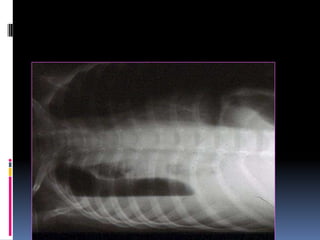

Underpenetrated Film

Hemi diaphragms are obscured

Pulmonary markings more prominent than they actually

Over penetrated Film

 Lung fields darker than

normal—may obscure subtle

pathologies

•   See spine well beyond the

diaphragms

•   Inadequate lung detail

Underpenetrated Film Hemi diaphragmsare obscured Pulmonary markings more prominent than they actually

Over penetrated Film Lung fields darker than normal—may obscure subtle pathologies • See spine well beyond the diaphragms • Inadequate lung detail